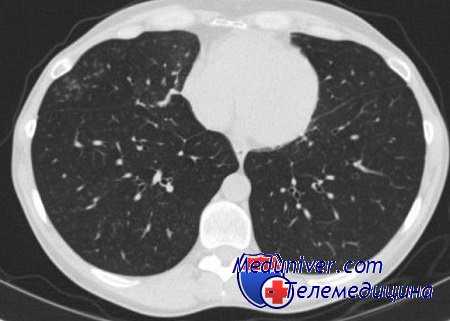

Сомнения позволяют разрешить сравнительный анализ газообмена при двулёгочном и однолёгочном вариантах ВЧС ИВЛ (рис. 2)

Рис. 2. Газообмен и гемодинамика при двулёгочном (ДВЧВ)

и однолёгочном (ОВЧВ) вариантах высокочастотной вентиляции.

Диаграммы рисунка 2 свидетельствуют о незначительных различиях в газообменном и гемодинамическом статусе двулёгочного и однолёгочного вариантов ВЧС ИВЛ. При двулёгочном варианте отмечаются достоверно более высокая оксигенация артериальной крови, что при одинаковых режимах вентиляции (f=100 циклов в минуту, VE=17 л, I:E=1:2) может быть связано только с меньшим вено-артериальным внутрилёгочным шунтом. Подтверждение данного положения потребовало специального исследования.